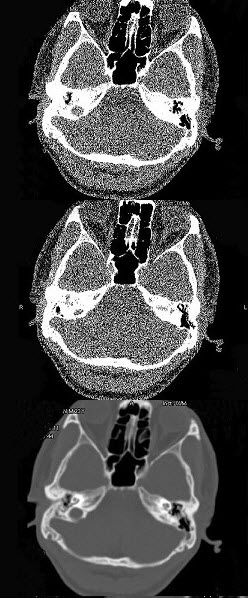

- 单项选择题男,23岁,右耳流脓十余年,右外耳道流脓,鼓膜穿孔,CT检查如图,最可能诊断为()。

A、慢性中耳乳突炎

B、中耳乳突结核

C、中耳癌

D、嗜酸性肉芽肿

E、海绵化期耳硬化症

- A